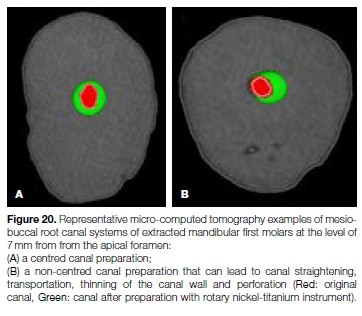

The ability of an instrument to stay centered in the canal can be measured by the mean centering ratio.23 The importance of maintaining preparations that are centered (Figure 20a) and correspond to the original canal anatomy has been pointed out by Berutti et al.24 A study by Pasqualini et al. examined rotary glide path files and concluded that files with a high root canal centering ability resulted in fewer modifications of the canal curvature and therefore fewer canal aberrations.25 Several studies have shown that more flexible instruments produce more centered preparations.26,27 Flexibility can be defined as the elastic bending of an endodontic instrument when subject to a load applied at its extremity in the direction that is perpendicular to its long axis.28

Flexibility may influence an instrument's ability to properly shape curved root canals. Inflexible files, on the other hand, may cause a deviation from the original canal axis, which can result in canal straightening, transportation, thinning of the canal wall and perforation (Figure 20A and 20B).